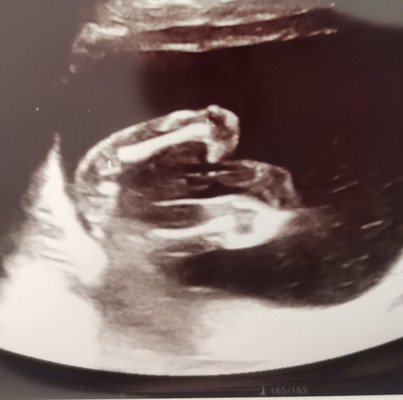

ผู้ หญิง หรือ ชาย คะ ซาวเมื่อ19 w แล้วค่ะอยากทราบเพศ มองไม่ขาดเลยค่ะ แม่ๆช่วยดูหน่อยนะคะ ขอบคุณค่ะ

ผู้หญิงหรือชายคะ

ผู้ชายค่ะ